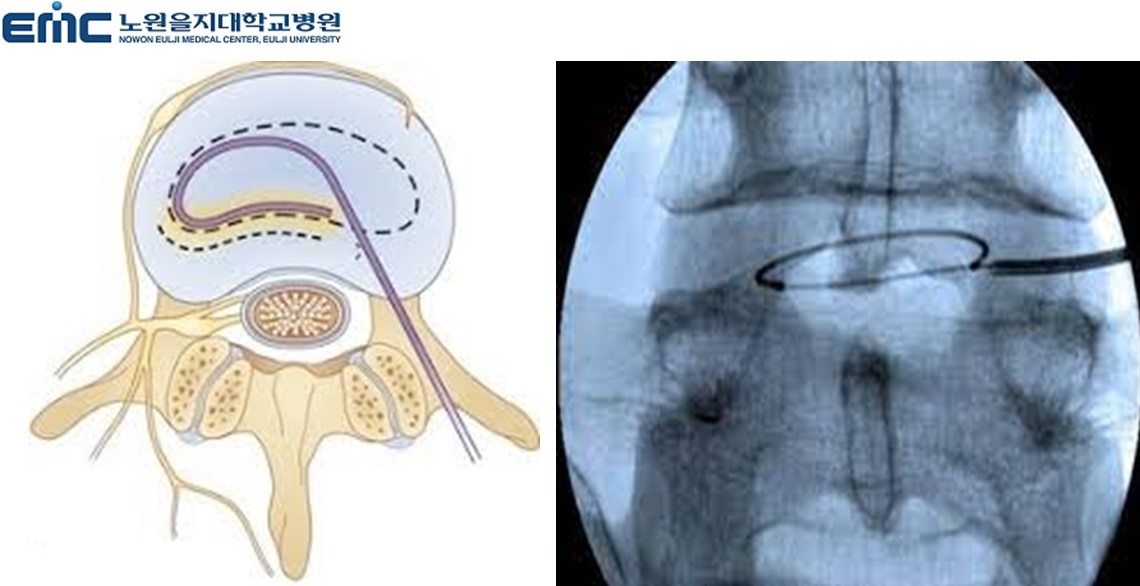

2. 풍선확장술

척추관 협착증으로 진단된 경우 꼬리뼈의 천추열공을 통해 특수 카테터를 병변 부위에 위치시킨 다음 카테터 끝에

있는 풍선을 부풀려 척추관의 공간을 넓혀주고 약물을 직접 병변에 주입하는 시술입니다. 통증이나 전신마취

필요성, 흉터, 출혈이 없으며 시술시 피부를 최소한으로 절개하여

풍선이 내장된 특수 카테터를 삽입하고 풍선을 부풀림으로써 좁아진 척추관을 넓히는 시술입니다.